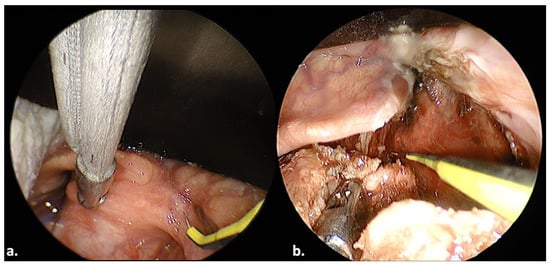

3.3. Case 7

3.4. Case 8